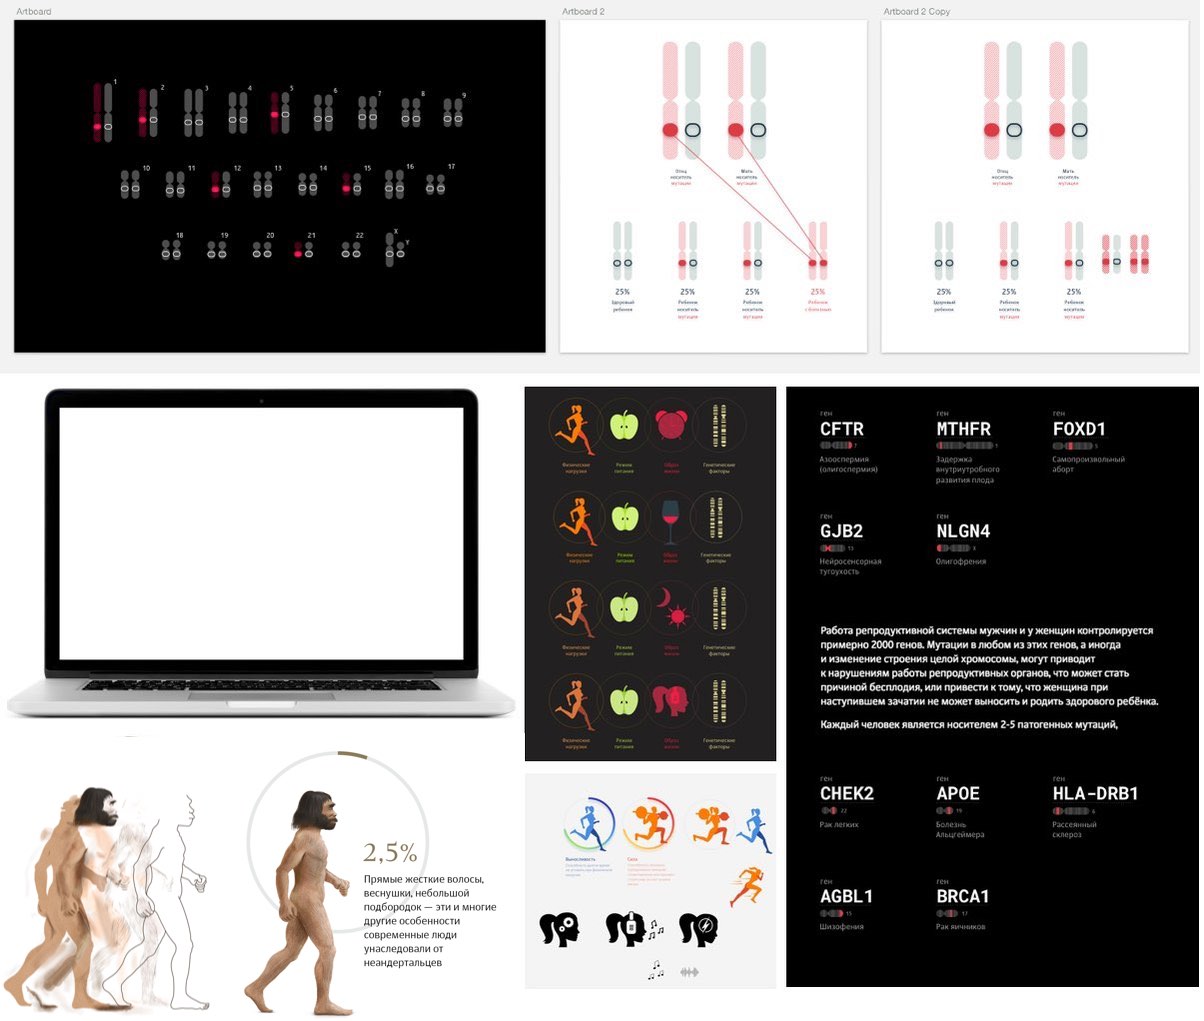

Considering a way to present genetics based on themes.

Deciding to drop all the abstract features for now. Trying to play with contrasting scales: a cell as a “genetic factory;” an eye as an illustration of a person’s congenital features with its color and shape; a ballerina as a representation of talent and realization of human abilities.

—an insert about genetic factors influencing that sphere of life;

The introduction is followed by a block about the influence of genetics on each sphere of human life. Drawing "the best illustration of a call on the internet."

Drawing additional icons and technical graphics.

Taking and retouching a bunch of photos, drawing more technical graphic elements.